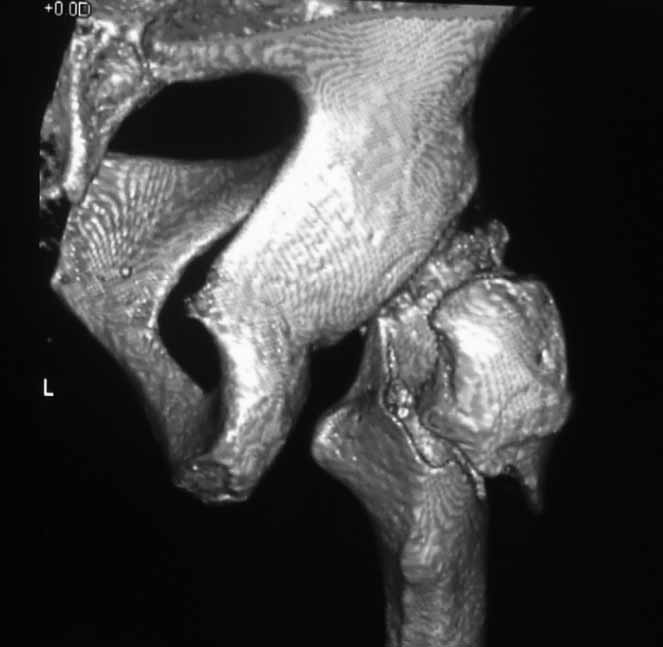

Пациентка 53 лет. ДТП 09.01.12: сочетанная травма: перелом 2-5 ребер справа, ушиб легких; перелом обеих лонных костей без смещения; закрытый перелом проксимального конца правой бедренной кости; открытый оскольчатый внутрисуставной перелом проксимальных концов костей правой голени.

В нашей клинике 11.01 выполнен минимально инвазивный остеосинтез большеберцовой кости (снимки до операции не перефотографировал) с пластикой перемещенными лоскутами дефекта, образовавшегося вследствие некроза кожи на передней поверхности голени. Бедро одномоментно делать не стал, не было уверенности в наличии перелома на уровне шейки. Во время операции смотрел тазобедренный сустав под ЭОПом, головка неподвижна. После операции повторили КТ, стало очевидно, что имеется субкапитальный перелом.

И еще: не явится ли препятствием для введения гвоздя дугообразный изгиб диафиза бедренной кости? Вершина деформации расположена на 110мм дистальнее проксимального края малого вертела. Это я по КТ измерил точно. Можно, конечно, думать о короткой ножке. Но обеспечит ли она достаточную фиксацию при таком переломе?